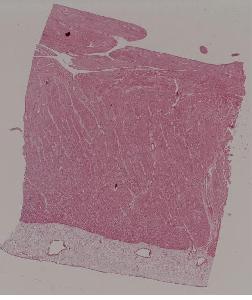

5. Fibrinoid necrosis of the arteriolar wall